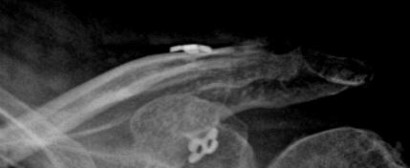

Distal Clavicle Fracture Repair with Buttons

Fracture on the left with the repair on the right.